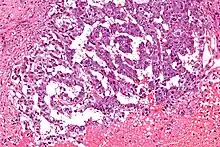

La tumeur du sac vitellin est une tumeur peu commune issue des cellules germinales qui reproduisent des structures extra-embryonnaires. Elle correspond à la tumeur maligne la plus fréquemment retrouvée chez l'enfant. Elle est caractérisée par une prolifération tumorale à cellules claires agencée en réseau et peut former des structures végétantes endoluminales. Cette tumeur est rarement bilatérale.